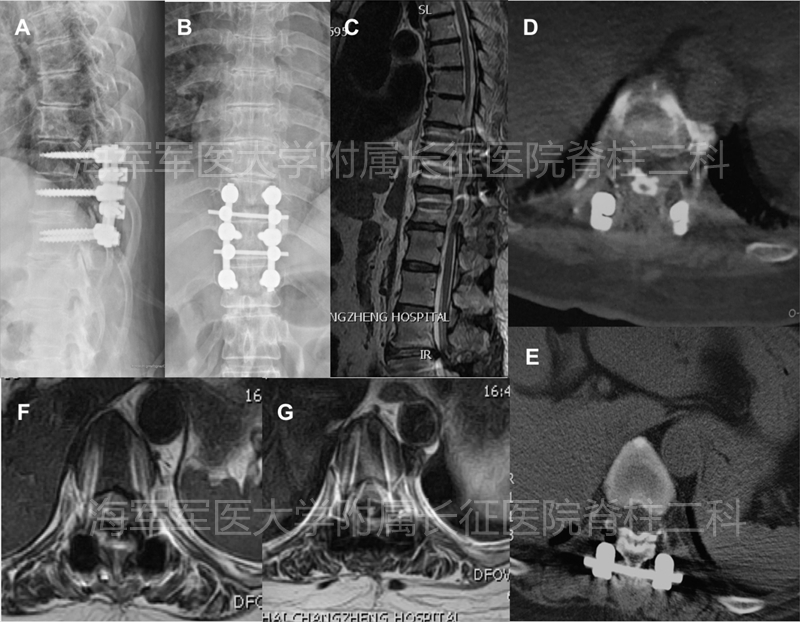

2.ACAF技术在颈胸段后纵韧带骨化症中的应用

术前、术后侧位平片对比

术前、术后矢状位CT对比

术前、术后水平位CT对比

术前术后矢状位MRI对比

术前术后水平位MRI对比